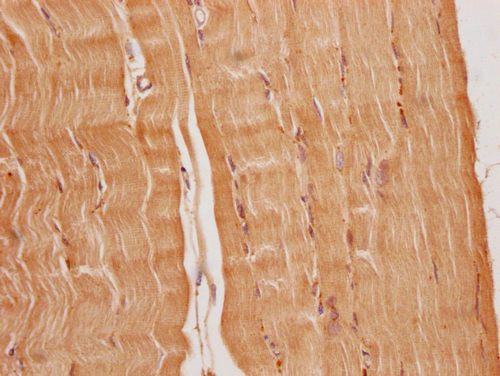

IHC image of CSB-PA836707OA01HU diluted at 1:200 and staining in paraffin-embedded human heart tissue performed on a Leica BondTM system. After dewaxing and hydration, antigen retrieval was mediated by high pressure in a citrate buffer (pH 6.0). Section was blocked with 10% normal goat serum 30min at RT. Then primary antibody (1% BSA) was incubated at 4°C overnight. The primary is detected by a Goat anti-rabbit polymer IgG labeled by HRP and visualized using 0.05% DAB.

IHC image of CSB-PA836707OA01HU diluted at 1:200 and staining in paraffin-embedded human skeletal muscle tissue performed on a Leica BondTM system. After dewaxing and hydration, antigen retrieval was mediated by high pressure in a citrate buffer (pH 6.0). Section was blocked with 10% normal goat serum 30min at RT. Then primary antibody (1% BSA) was incubated at 4°C overnight. The primary is detected by a Goat anti-rabbit polymer IgG labeled by HRP and visualized using 0.05% DAB.